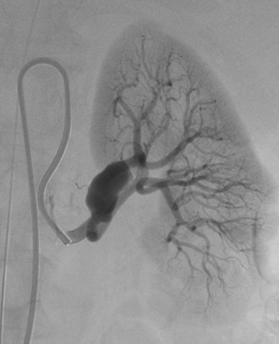

Treatment of complex aneurysms: Treatment of complex intracranial aneurysms often involves balloon-remodeling, stent-assisted coiling, or flow diverters. These methods can also be used for non-neurovascular procedures, specifically in treatment of visceral aneurysms. Renal artery aneurysms are most frequently located in the renal hilum, where the main renal artery diverts into its ventral and dorsal branch. Preservation of all renal artery branches may request advanced techniques as mentioned above (1); Fig 1,2.

Fig. 1: Balloon assisted embolisation of a broad based renal artery aneurysm

Fig. 3: Successful exclusion of the aneurysm with preservation of both renal artery branches